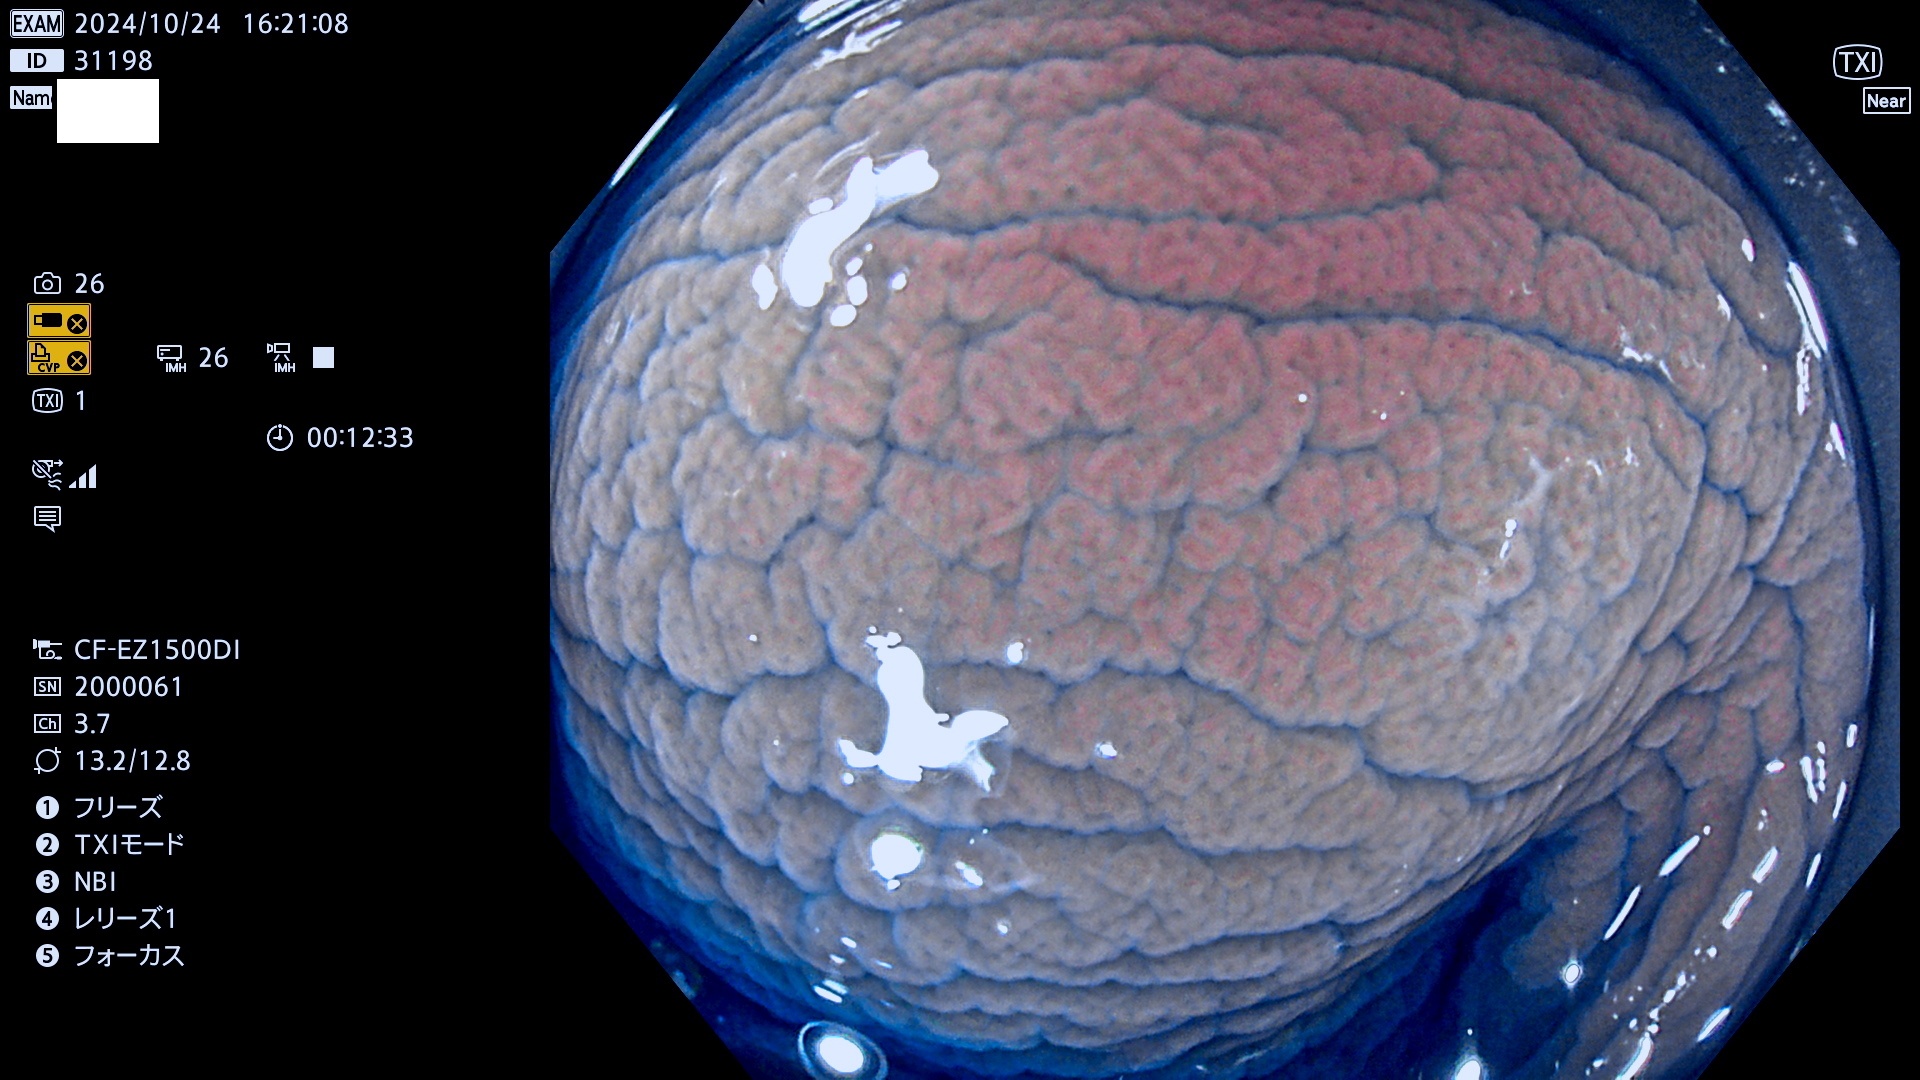

完全に平坦な物をUb、陥凹している物をUcと呼びます。最も発見が難しく危険な病変です。

毎週の検査(木・金・土・日)に発見されたUb、Uc型・腺腫を、その週の日曜の夜にUPし1週間、提示します。

抽出の対象期間 2024年10月24日〜10月27日の4日間(48件の検査)7件 (7/48=15%)